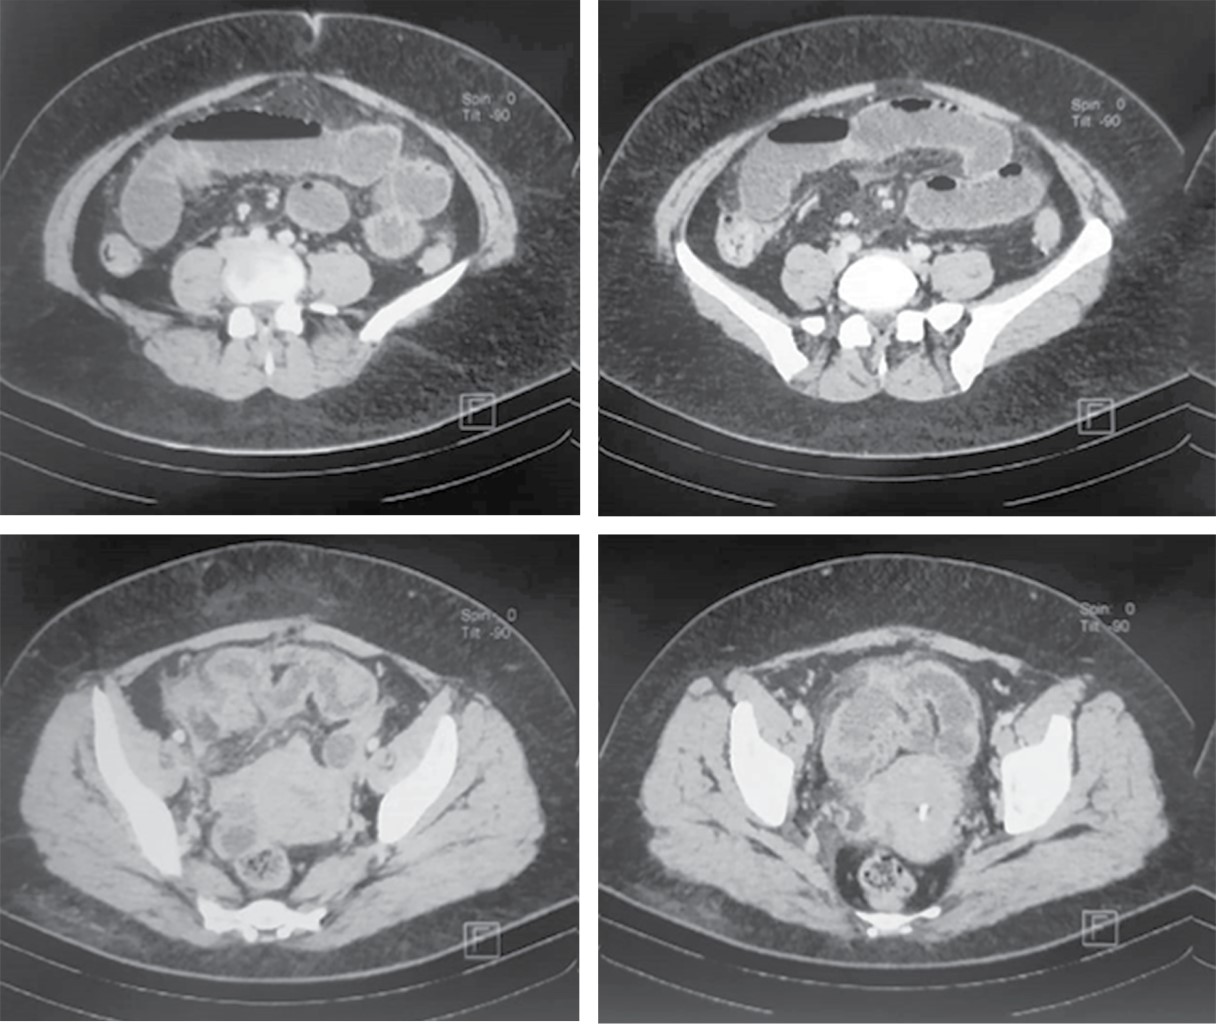

This is the case of a 47-year-old female patient with no relevant medical history. She smoked 20 cigarettes per day with a smoking index of 25, which is considered as a major risk for chronic obstructive pulmonary disease (COPD); she had an elective cesarean section 13 years ago. Her condition began four days prior to her evaluation, when she presented pain in the epigastrium of intensity 7/10 without irradiation, without triggering or exacerbating factors; it was accompanied by nausea and vomiting of food content on five occasions. Twenty-four hours after the onset of the symptoms, she reported having self-medicated with the antispasmodic drug butyl-hyoscine 10 mg every 12 hours, after which she had a slight improvement, so she was left to free evolution. 48 hours later she presented increased vomiting, as well as abdominal pain that had migrated to the right iliac fossa. She did not report having fever. She went to a private hospital 72 hours after the onset of the symptoms, where amikacin as antibiotic was administered along with an analgesic drug and metoclopramide at unspecified doses, without relieving the symptoms. At another private hospital where she was taken because of increasing intensity of abdominal pain, laboratory studies were performed that showed: a white blood cell count of 23.3 × 103/μl with a neutrophil count of (19.48 × 103/μl). The rest of the laboratory parameters were within normal range values. Once acute appendicitis was suspected, a contrasted thoraco-abdominal-pelvic CT scan was requested, which showed signs of a probable acute appendicitis complicated with a localized abscess, as well as findings of air bronchogram and data suggestive of atypical pneumonia due to SARS-CoV-2 (Figures 1 and 2), so it was decided to send her to the emergency department of our hospital unit.

Figure 2